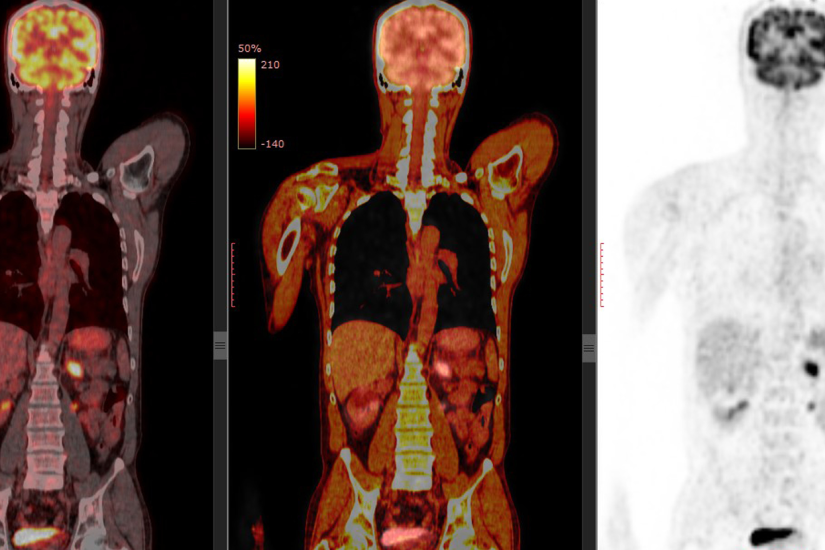

Combinarea acestor investigatii cu tomografia computerizata (CT) permite obtinerea unui diagnostic mai exact printr-o singura examinare (ca de exemplu, PET/CT). Prin informatiile pe care fiecare test le aduce, aceste examene sunt complementare, permitand evaluarea unei leziuni atat din punct de vedere functional (medicina nucleara, PET), cat si anatomic (CT).

Un echipament hibrid care produce atat scanari PET, cat si CT ale acelorasi regiuni ale corpului intr-o singura examinare (PET/CT) a devenit principala metoda imagistica pentru stadializarea majoritatii cancerelor la nivel mondial.

Scopul principal al PET/CT este de a evalua pacientii cu cancer, investigatia avand un rol important in:

- Diagnosticul cancerului

- Depistarea precoce a metastazelor (stadializare)

- Evaluarea eficacitatii tratamentului

- Identificarea recidivei tumorii

In prezent, in lume sunt utilizati mai multi radionuclizi emitatori de pozitroni. In ultimii 15 ani, moleculele de glucoza radiomarcate usor modificate (deoxiglucoza marcata cu fluor F-18 sau 18F-FDG) s-au dovedit a fi cel mai bun trasor disponibil pentru detectarea cancerului si a raspandirii metastatice a acestuia in organism.

Celulele canceroase fiind active din punct de vedere metabolic au nevoie de mai multa energie decat celulele normale. Drept urmare, absorb mai multa glucoza. Radiotrasorul FDG (fluorodeoxiglucoza) este un compus similar cu glucoza. Celula maligna va consuma glucoza radiomarcata in cantitate mare, iar energia emisa va fi detectata de dispozitivul PET cu obtinerea de imagini care evidentiaza locatia radiotrasorului in corp.